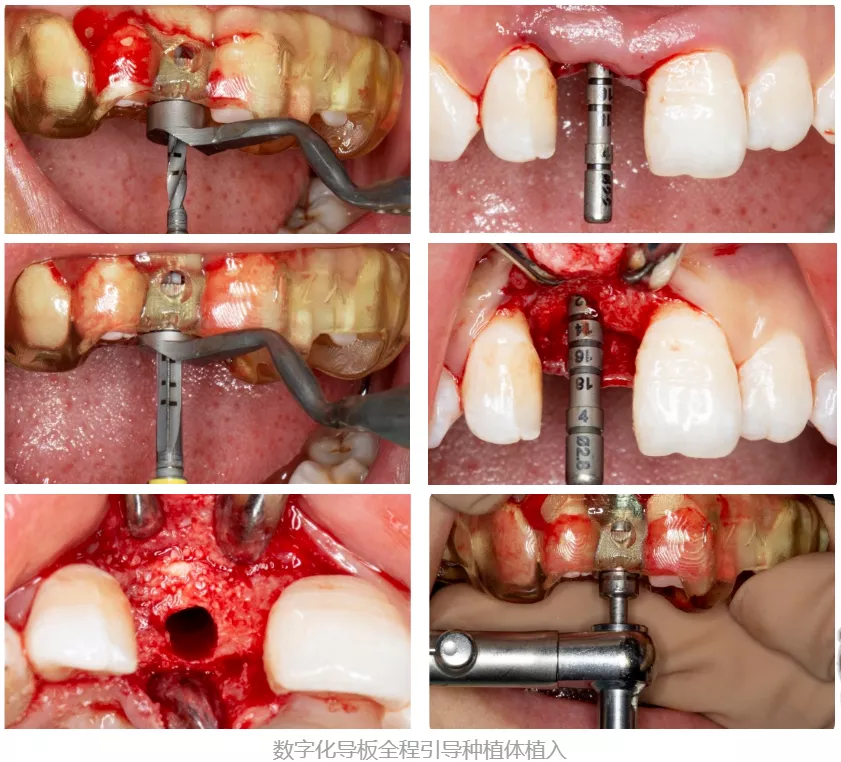

第三阶段:全程数字化引导下的手术实施

·      全程数字化手术导板引导下的种植手术。

·      术后CBCT显示种植体方向位置良好,唇舌侧骨壁完整。